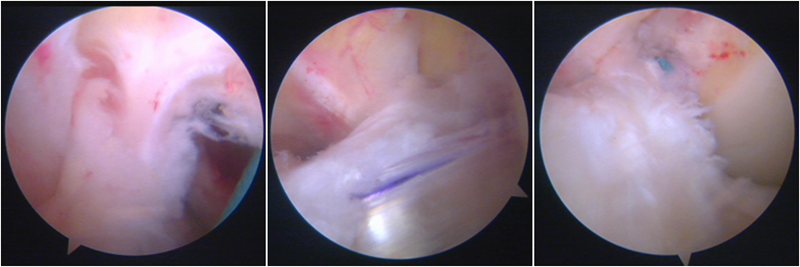

韧带导入过程

送止血带后韧带表明血管膜